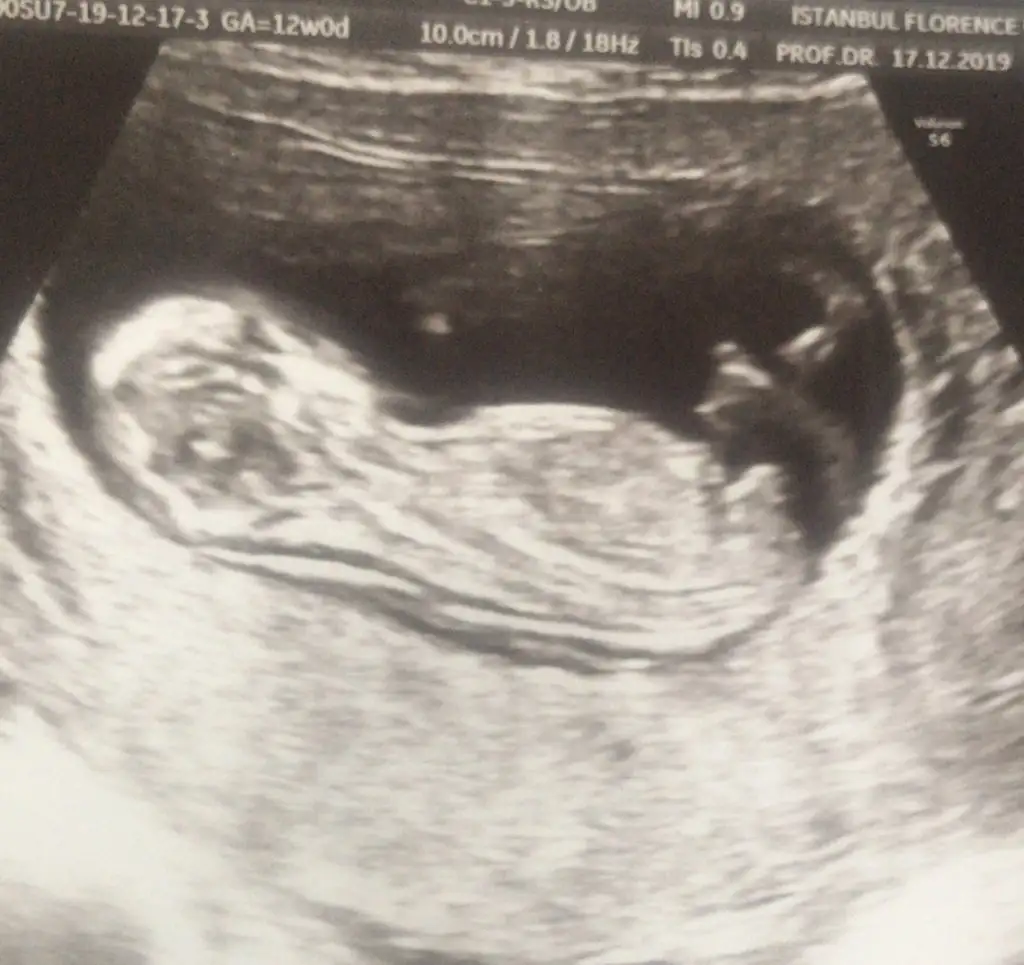

dr soylemeden siz gorun genital nub teorisi ( bebegin cinsiyeti)

• 20191217_220012.webp

20191217_220012.webp

12,3 KB · Görüntüleme: 35